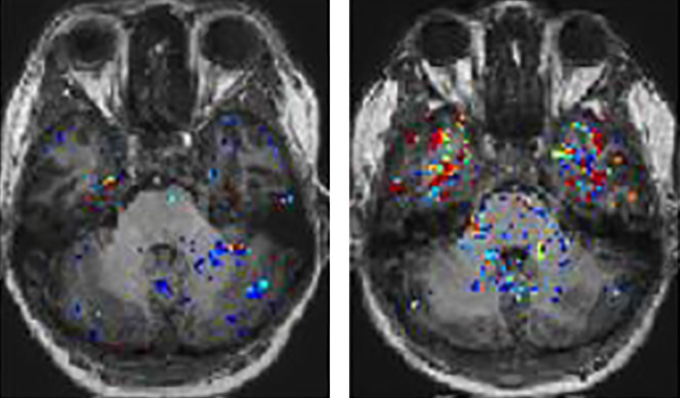

Leakiness in the brain could explain the memory and concentration problems linked to long COVID.

Brain fog is a debilitating symptom commonly reported by people with long COVID. Now, scientists have linked the symptom to leaky boundaries in the brain.